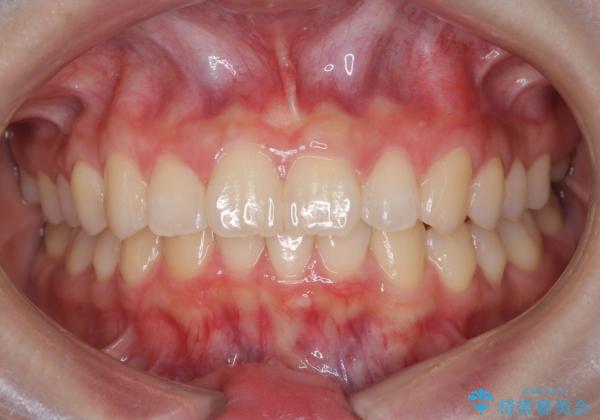

【インビザライン】前歯を下げたい。

- 前歯が出ていることを主訴に来院されました。

下顎前歯が1本欠損していることもあり、前突はある程度残ることを説明し、インビザラインにて治療を行いました。

今回は抜歯矯正ではなく歯列弓の拡大とIPR、遠心移動を行って配列することができました。

口元も改善し患者さんには喜んでいただけました。

下顎前歯が1本少ないため、上下の正中は合いません。